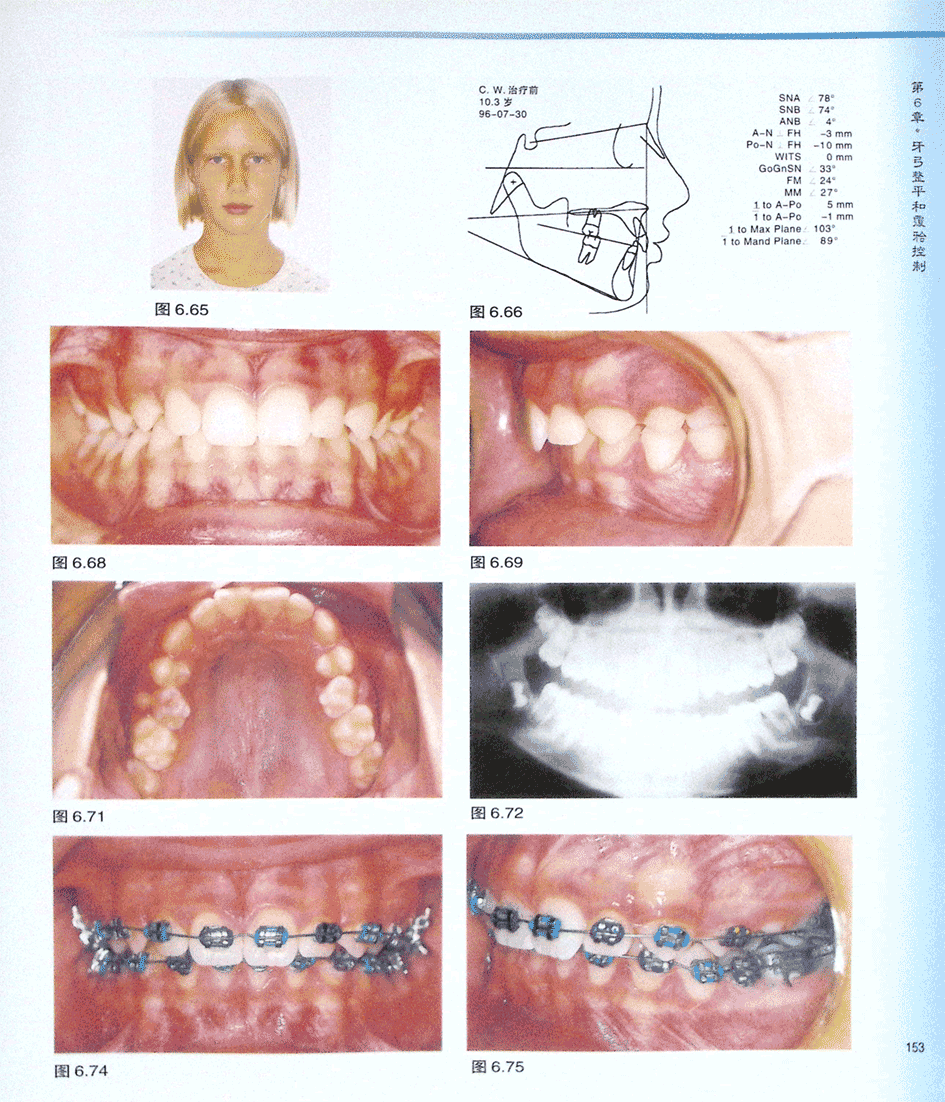

病例CW 非拔牙矫治深覆牙合(一)